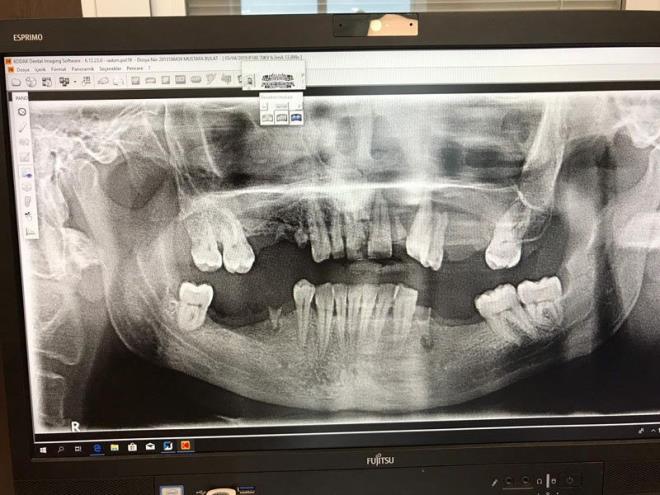

9. Para koparma iddiası: Hastanın ve ailesinin derdinin para koparmak olduğunu ileri süren A.P. “Aileye bize de bilgi verin dedik. Aradan 15 gün geçti bilgi alamayınca, ben kendi telefonumdan arayarak bilgi istedim. Ayrıca şayet çekilen diş sonucu bu olay yaşansa bile biz o bölgeden diş çekmedik daha önce çekilmiş zaten, röntgende de var bunlar. Bu olay iltihaplık diş çekimiyle olan bir olay değil. Bunların amacı yönlendirme ile hekimi tacizle para koparmak, biz bunu anladık. Biz teşekkür beklerken bu tepkilere maruz kaldık” ifadelerini kullandı.

Para koparma iddiası: Hastanın ve ailesinin derdinin para koparmak olduğunu ileri süren A.P. “Aileye bize de bilgi verin dedik. Aradan 15 gün geçti bilgi alamayınca, ben kendi telefonumdan arayarak bilgi istedim. Ayrıca şayet çekilen diş sonucu bu olay yaşansa bile biz o bölgeden diş çekmedik daha önce çekilmiş zaten, röntgende de var bunlar. Bu olay iltihaplık diş çekimiyle olan bir olay değil. Bunların amacı yönlendirme ile hekimi tacizle para koparmak, biz bunu anladık. Biz teşekkür beklerken bu tepkilere maruz kaldık” ifadelerini kullandı.